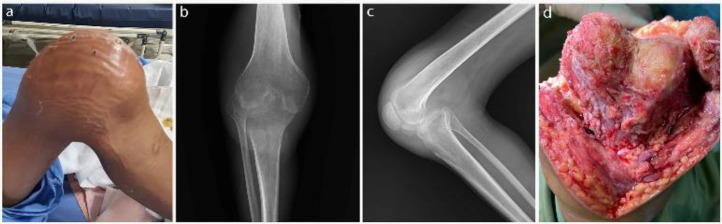

Neglected knee dislocations are rare and challenging orthopedic injuries. We report using a traction pin to treat a neglected knee dislocation and a concurrent infection. Following the primary reduction with extensive soft-tissue release, a proximal tibial traction pin was used to obtain complete reduction via traction weight change.‎ No ligamentous repair was done for the patient. The patient's one-year follow-up showed an acceptable radiographic reduction supported by satisfactory clinical outcomes. In conclusion, the proximal tibial traction pin could be a good alternative for treating neglected knee dislocations. It makes future knee replacements more practical, a significant concern in such patients. Meanwhile, it is much more affordable than the other available techniques.